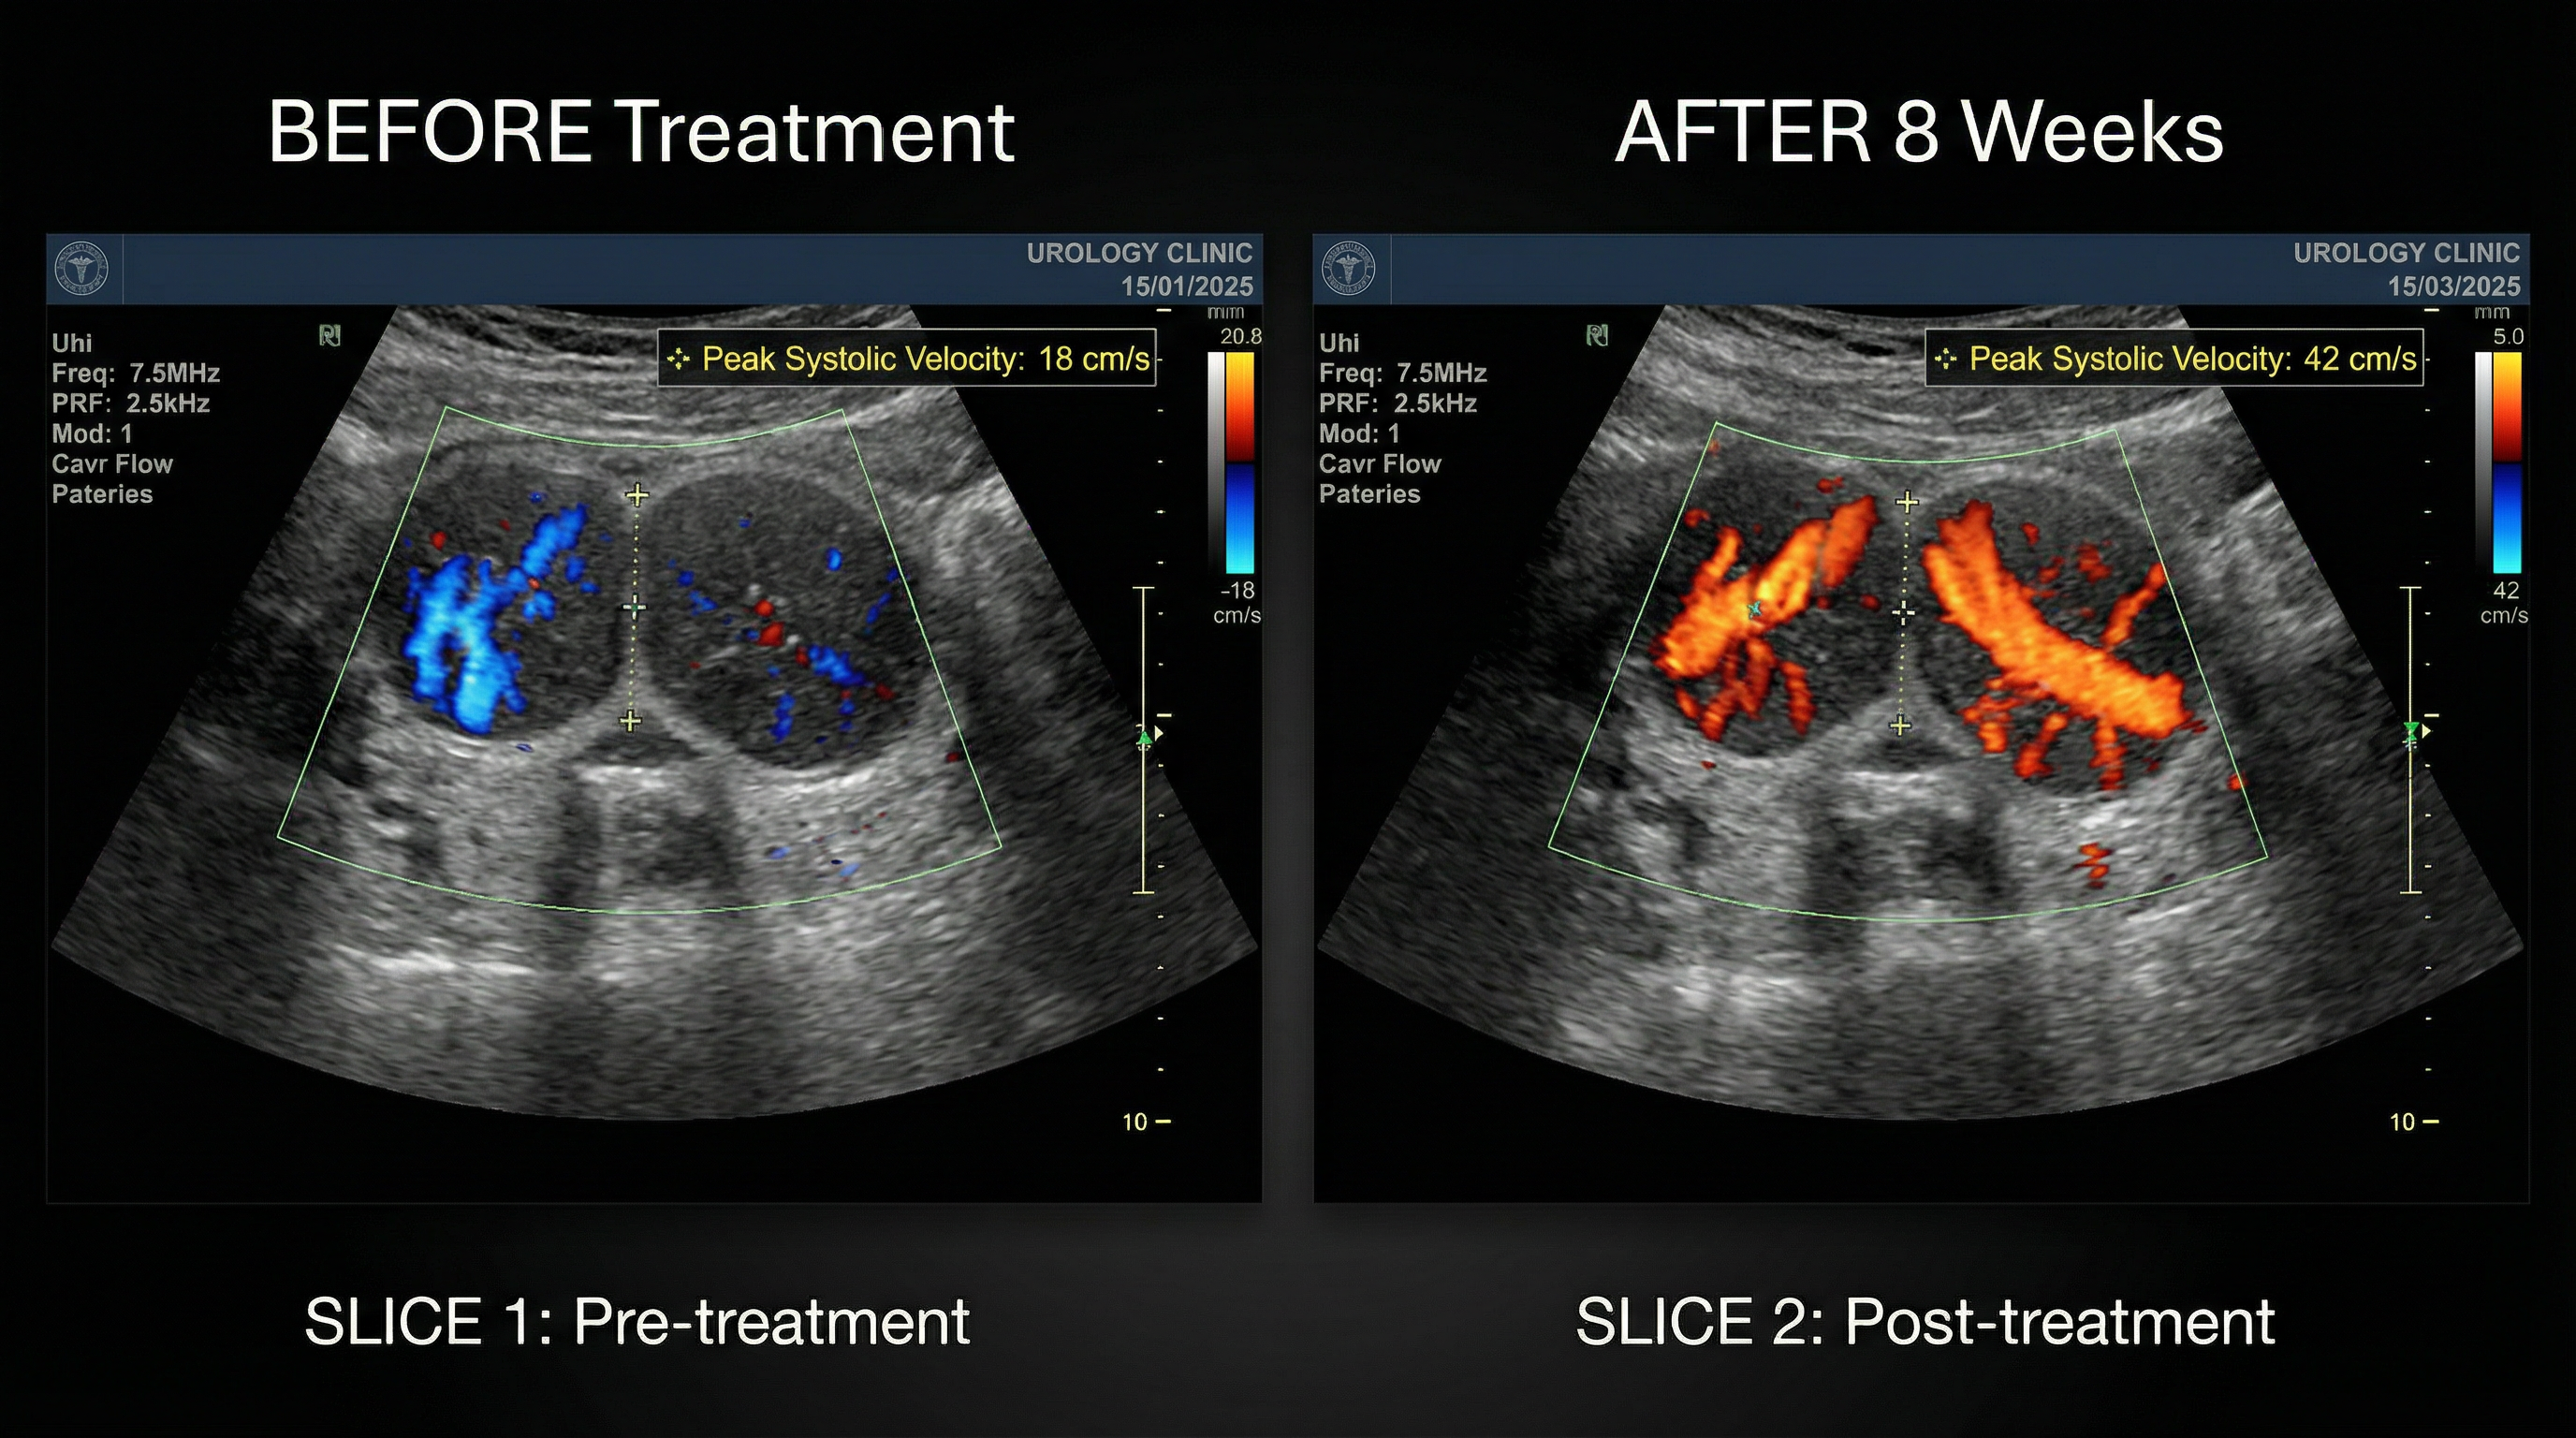

Real clinical imaging. Real results. Doppler ultrasound confirms 133% improvement in blood flow after 8 weeks of LumiFlex™ use.